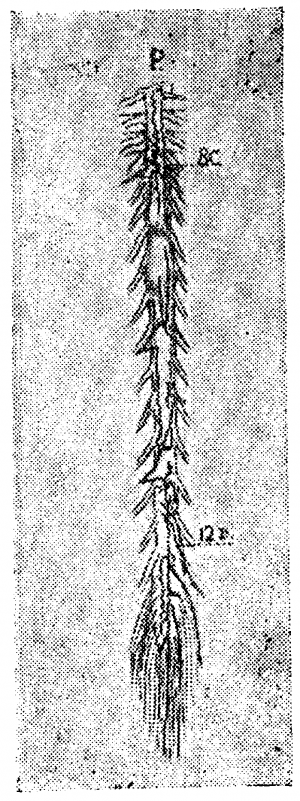

Вены вещества спинного мозга (рис. 1). Центральные вены, подобно артериям, бывают правые и левые, то есть выносят кровь из (какой-либо одной половины серого вещества. В отличие от соответствующих артерий, они анастомозируюг между собой. Возникают они из мелких веточек, близких по калибру к артериолам, и сами являются очень мелкими тканевыми сосудиками. Поллак отмечает, что в сером веществе спинного мозга очень редко встречаются относительно более крупные венозные сосуды: мелкие веточки почти непосредственно собираются, в относительно крупный стволик центральной вены. Центральные вены впадают в передние венозные тракты или вернее они образуют их. Вены белого вещества спинного мозга крупнее соответствующих артериол и центральных вен (вен серого вещества). В отличие от артерий вены серого и белого вещества богато анастомозируют между собой, так что кровь из серого вещества может изливаться двумя путям: через передние и через боковые и задние тракты, чем и объясняется относительно малый калибр вен серого вещества и кажущееся нарушение правила о превосходстве площади сечения вен над площадью сечения соответствующих артерий.

Мы уже неоднократно упоминали о работе Словохотова, исследовавшего развитие сосудов спинного мозга в эмбриональный период и показавшего, что закладка сосудов в эмбрионах проходит по эмбриональному типу, который ещё ясно выражен до 6-го лунного месяца. Во вторую половину утробной жизни происходит перестройка метамерного типа на стволовой (рис. 3 и 17).

По нашим исследованиям, у новорожденных строение вен спинного мозга уже приобретает все основные характерные черты, свойственные взрослому; мы можем совершенно определённо констатировать наличие продольных стволов, вены корешков выражены ясно, неравномерны по калибру и неравномерно распределяются.

В возрасте 4—5 месяцев внеутробной жизни, мы видели уже богато развитую поверхностную венозную сеть, но она ещё очень тонка, почти капиллярна. Передний средний венозный тракт вполне сформирован; боковые тракты намечаются на нашем препарате спереди, в грудном отделе спинного мозга. Вены спинно-мозговых корешков выражены хорошо, но ещё сохраняют эмбриональный тип в том отношении, что вены главных оттоков (корешков шейного и поясничного утолщения) ещё не так резко преобладают над другими корешковыми венами, как это бывает у взрослых.

Большая вена Адамкевича типично отходит от среднего переднего венозного тракта, очень хорошо развитого.

Задняя поверхность мозга на том же препарате представляет более пёструю картину: шейная часть задней поверхности покрыта тончайшей сетью вен, но продольное расположение сосудов по корешкам и задней расщелине уже намечается. Грудная часть препарата особенно интересна: с 8-м шейным корешком отходит (типично) вена спинно-мозгового нерва; сверху она соединена с венозными стволиками шейной сети, а книзу проходит в виде крайне извитого, часто пересекающего медиальную линию сосуда. Вены некоторых корешков (например, 2, 4 грудного) начинаются двумя корнями — верхним и нижним, так что намечается боковой тракт. Средний венозный тракт выравнивается в грудной области и змеится вдоль средней линии, причём на протяжении 6—7 грудных сегментов его сопровождает параллельный, уже хорошо сформированный стволик, спускающийся вдоль входа в мозг задних корешков. Оттоки в поясничной области развиты хорошо на 12-м грудном справа и на 1—2-м поясничных корешках слева.

В более старшем возрасте можно наблюдать уже вполне типичную для взрослых картину поверхностных вен спинного мозга.